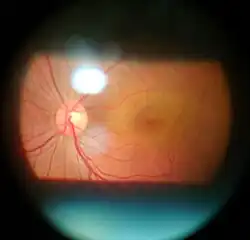

Diagnosis

Eye examination

Following are examples of examination methods performed during an eye examination that enables diagnosis

- Ocular tonometry to determine intraocular pressure

- Refraction assessment

- Retina examination

- Slit lamp examination

- Visual acuity

- Color vision test

- Visual field test

- Dry eye test

- Corneal topography

Specialized tests

Optical coherence tomography (OCT) is a medical technological platform used to assess ocular structures. The information is then used by eye doctors to assess staging of pathological processes and confirm clinical diagnoses. Subsequent OCT scans are used to assess the efficacy of managing diabetic retinopathy, age-related macular degeneration, and glaucoma